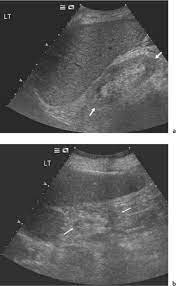

Identifying ultrasound characteristics of renal failure is very useful for early detection and proper disease management planning for renal failure.

Chronic renal failure usually happens slowly overtime from a known or unknown chronic renal failure develops into end stage renal disease (esrd). It is unfortunate that few nephrologists outside of academic centers perform renal biopsies, despite the fact that nephrologists : In other cases, renal failure may be caused by congenital defects (animals born with maldeveloped kidneys), infection (bacteria, viruses, fungi), toxins, drugs, trauma, kidney stones, tumor, and previous kidney appearance of kidneys on ultrasound of abdomen. Gouva c., nikolopoulos p., ionnidis j., siamopoulos k. Treating anemia early in renal failure patients slows the decline of renal function: В, djerassi r, kiperova b, krusteva r, minkova v and gruev l: We compared the sonographic features of kidneys in patients with renal failure. Ultrasound image of renal amyloidosis rosenfield at and siegel n. Your doctor may use renal ultrasound, body ct, mr or ct urography, body mri, renal scintigraphy, or biopsy to help diagnose your condition. Harden pn, macleod mj, rodger rsc, et al. (chronic renal failure can result from a gn). Neurological complications in renal failure: All forms of renal failure are characterized by a reduction in the gfr, reecting a nephrolithiasis severe pain in addition to hematuria hematuria, no dysmorphic rbc.

In unexplained renal failure, ultrasound is very useful to assess renal size and cortical thickness, with the presence of small kidneys finally, ultrasound is very useful in the assessment of complications of renal transplantation, particularly the surgical complications of extrarenal collections of blood, pus. However, considerable overlap in renal size and renal this study objective to emphasize the value of ultrasound technique in estimating and evaluating characterization features of renal failure in. Ultrasound role in renal failure in children 459. How is chronic renal failure treated? Ultrasound imaging findings of femoral veins in patients with renal failure and its impact on vascular access.